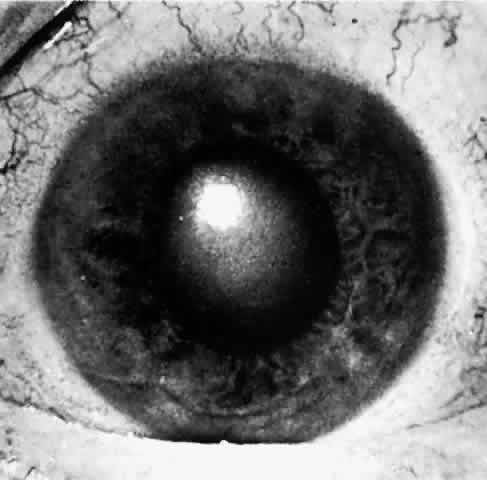

When a patient is seen after an attack that has been in progress for several hours or even days, the eye usually will display decreased vision. The pupil is irregular in shape, nonreactive to light, and resistant to the effects of miotics or mydriatics. It is a common misconception that the intraocular pressure remains elevated in angle-closure glaucoma. In some cases, low tension may be found after aqueous production has decreased while the angle remains closed. If the eye has recovered spontaneously from an attack, the intraocular pressure may be very low due to reduced aqueous formation with or without an open angle. It is important to realize that low pressure following elevated pressure due to acute angle-closure glaucoma does not necessarily mean that the angle-closure attack is over. The pressure will rise as soon as aqueous production resumes, which may be a few hours to many weeks later. The cornea may show Descemet's folds and later recover its transparency but occasionally the corneal edema may persist for weeks after reduction of intraocular pressure. A prolonged iris stromal edema encourages the formation of posterior synechiae in the pupillary area and peripheral anterior synechiae at the level of the angle structures. The destruction of iris tissue results in grayish patches of atrophic iris stroma that may extend to the periphery (Figs. 9 through 11). Tiny white-gray spots with discrete edges may be seen in the pupillary zone. These anterior subcapsular lenticular opacities, best known as glaukomflecken, appear to be the result of damage to the anterior lens epithelium from very high intraocular pressure (Fig. 12).35 Glaukomflecken may result from very high intraocular pressure of any etiology, but are especially characteristic of previous attacks of angle-closure glaucoma.

Fig. 9. Iris atrophy, presumably due to iris ischemia, commonly occurs in sever and prolonged acute angle-closure glaucoma. In this eye, gray, thin, depigmented areas of atrophy of the iris, most marked at the arrows, are present around the pupillary margin clockwise from 8 o'clock to 3:30. Iris atrophy from high intraocular pressure in angle-closure glaucoma usually involves irregular radial sectors of the iris and is most marked near the pupil. In these sectors, the pupil is usually permanently fixed and dilated as a result of the atrophic process.

Fig. 10. In this eye, iris atrophy due to neglected angle-closure glaucoma is so extensive that the pupil is fixed in wide dilation. Some pigment granules from the atrophic iris lie scattered about on the iris stroma. There is a posterior synechia at 2 o'clock at the iris margin. Glaukomflecken are very numerous in this eye but are not visible in this photo because oblique slit illumination is not used; they are visible in Figure 12, in which proper illumination is used. (Photographed by Dr. David Donaldson)

Fig. 11. Same eye as is shown in Figures 10 and 12. This gonioscopic view shows much pigment debris released by the atrophic process in the iris on the angle wall. The pigment seen lies on the angle wall between Schwalbe's line anteriorly and the synechial attachment of the iris. Throughout the portion of the angle in this photo, synechiae attach at the level of the anterior trabecular meshwork, covering the ciliary band, scleral spur, and posterior trabecular meshwork and obstructing all useful outflow from this portion of the angle. (Photographed by Dr. David Donaldson)

Fig. 12. Same eye as shown in Figures 10 and 11. With oblique slit-lamp illumination, glaukomflecken of Vogt appear as pleomorphic gray-white patches just beneath the anterior lens capsule. These are presumed to be areas of necrotic lens tissue caused by very high pressure. With time, they lie deeper and deeper beneath the anterior lens capsule as new lens fibers are laid down, but they will persist permanently as silent records of previous high intraocular pressure. (Photographed by Dr. David Donaldson)